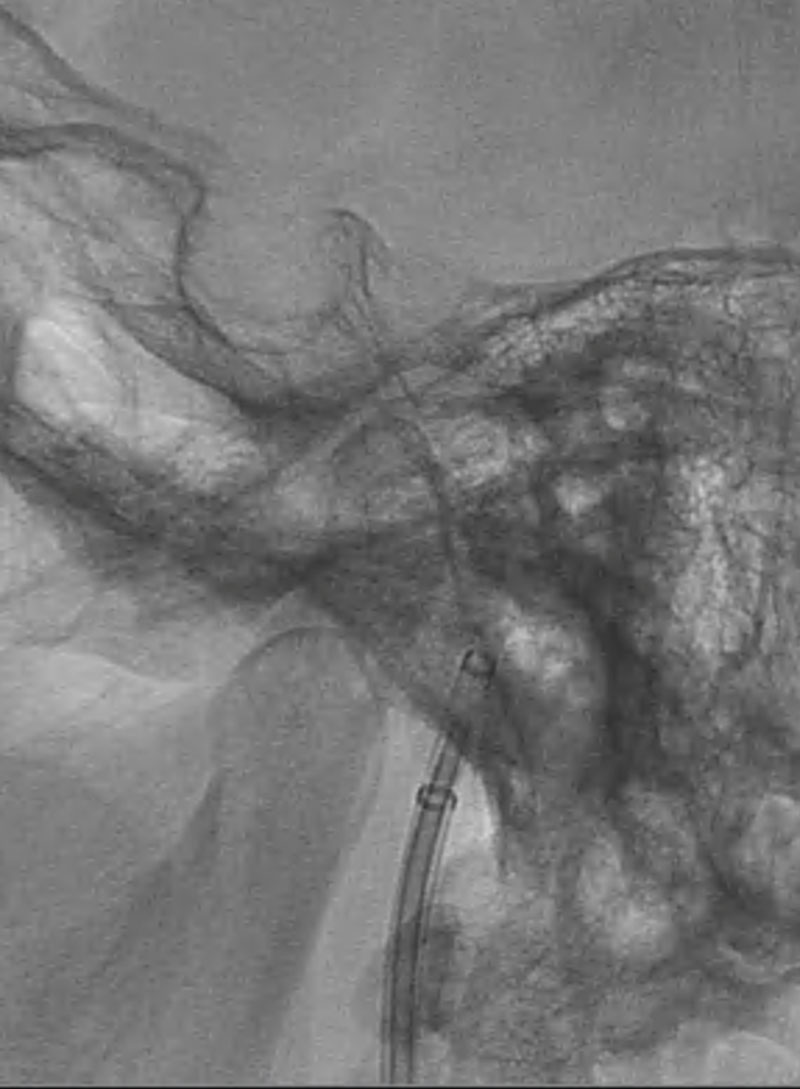

VASO-CT post

24h CT-scan

24h CTA and CTP

6 months DSA follow up